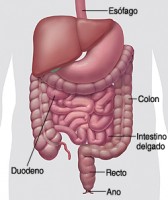

¿Dónde se desarrolla el Gist?

Los Gist se pueden desarrollar en cualquier parte del tracto gastrointestinal:

- Entre el 50-70% de todos los Gist se originanen el estómago.

- Entre el 20-30% en el intestino delgado.

- Entre el 5-15% en el intestino grueso y recto.

- En casos aislados, menos de 5%, también se pueden encontrar en el esófago o en la cavidad abdominal.